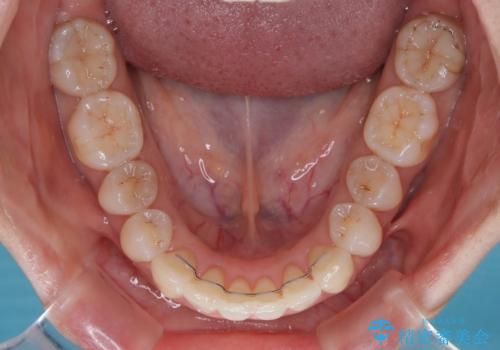

補助装置を用いて奥歯の咬み合わせを事前に改善 インビザラインによる矯正治療

歯列としてはインビザラインでもワイヤー矯正でも対応できるものでしたが、奥歯の咬み合わせを見た時に上顎がやや前方にあり、インビザライン単独では時間のかかってしまう可能性があるため、補助装置を治療当初に使用することで、インビザラインによる治療をスムーズに行えるように計画しました。

インビザラインは得意・不得意の差がはっきりとしているため、補助装置やワイヤー装置などをうまく活用することで、治療期間を短縮するとともに、より理想的な仕上がりを達成することができます。